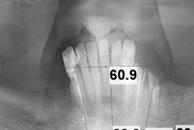

En la ortopantomografía se aprecia una dentición permanente a falta de la erupción de los 2os y 3 os molares, así como una asimetría ósea con rama y cóndilo mandibular izquierdo menos desarrollado (figura 9), causante de la asimetría facial descrita anteriormente.

El estudio cefalométrico (figura 10) revela una Clase II esquelética por hipoplasia mandibular, patrón braquifacial e incisivos superiores muy protruidos (14,9 mm) y

Figuras 9-11.

vestibulizados (52º), e inferiores lingualizados (16 º). El perfil es extremadamente convexo.